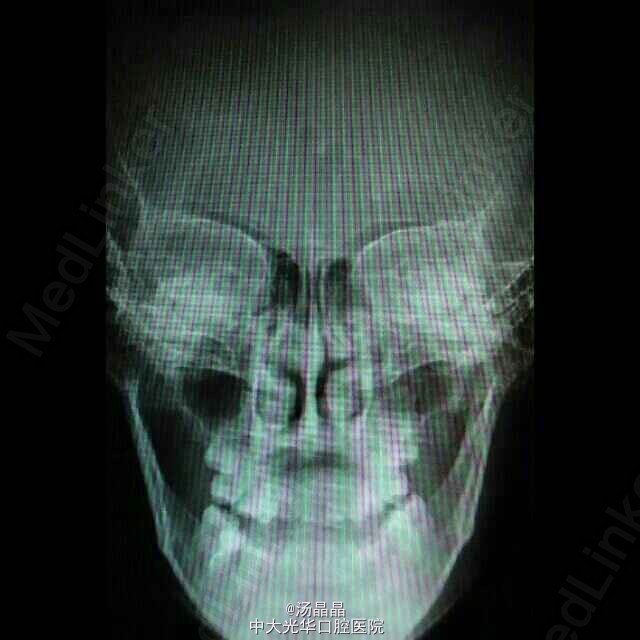

患者青年女性,上颌后缩,下颌前突6年,随发育渐进加重

面下三分之一长面型,侧面严重凹面型,上颌后缩,下颌前突,双侧颞下颌动度一致,无压痛,未闻及弹响和杂音,全口牙齿见正畸托槽,16.11.21.25.36.46缺失,中线齐,全牙弓反合,反覆盖大于3cm